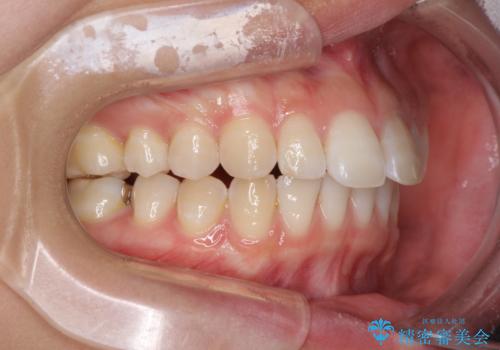

- 変色した前歯と突出した口元を気にして来院された患者様です。

口元の突出感はインビザラインにより歯列を整え、その後に、前歯をオーダーメイドタイプのオールセラミッククラウンにて補綴治療することとしました。

長時間のマウスピース装着と、患者様自身でのゴムかけに協力いただき、口元の突出感をしっかりと改善することができました。

前歯のオールセラミッククラウンもまるで本物の歯のように仕上がり、患者様には大変満足していただきました。